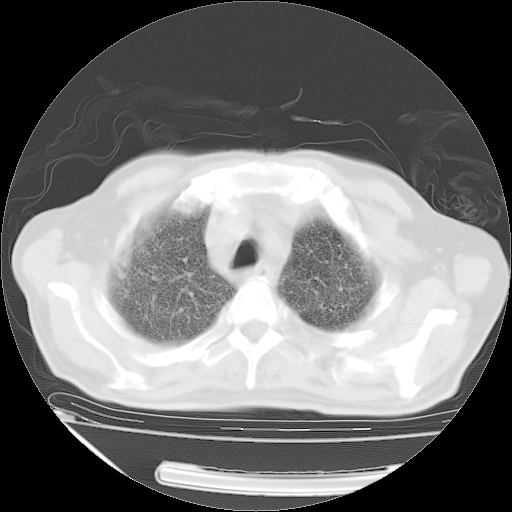

甲强龙80mg/日+抗结核治疗(异烟肼+利福霉素+乙胺丁醇)10天。复查肺部CT。

治疗10天肺部CT